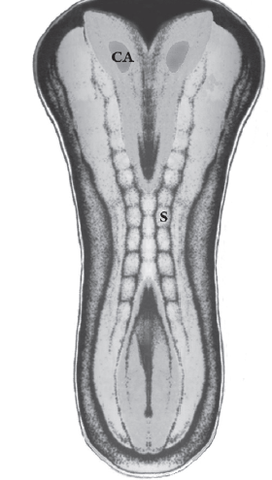

Al comienzo del período somítico aparece en el neuroectodermo un engrosamiento a cada lado de la extremidad anterior de la placa neural, es el denominado campo o área ocular. Cada campo ocular comienza a evaginarse formando el surco óptico.

Cuando se completa el cierre del neuroporo anterior, alrededor del día 25 del desarrollo, el esbozo óptico aparece como un divertículo lateral del prosencéfalo, denominado vesícula óptica

La vesícula óptica está relacionada con la formación de

la placoda cristaliniana. Ésta se invagina, constituyendo la vesícula cristaliniana. Al mismo tiempo, la porción distal e inferior de la vesícula óptica se deprime de forma gradual para formar una invaginación con dos capas, interna y externa, denominada cúpula óptica. Esta invaginación recorre longitudinalmente el pedículo óptico formando una hendidura conocida como hendidura

embrionaria